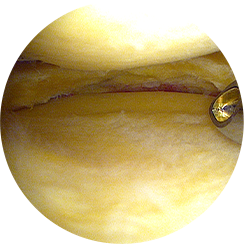

특수 미세 기구를 이용해

손상된 부위를 절제하거나,

봉합합니다.

고해상도 영상으로

연골·인대·반월상연골의

손상 부위를 정확히 확인합니다.